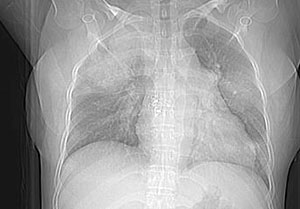

女性,30岁。

病史为胸痛20多天,无畏寒发热,无消瘦,无咳嗽咳痰。总之症状很逍遥。

临床以胸痛待查收住入院。

平片拟诊转移瘤。

双肺野可见散在大小不等结节及肿块影,内密度不均匀,边缘部分清,部分欠清,纵隔未见明显肿大淋巴结.右侧胸腔少理积液.结合临床,考虑韦格肉芽肿可能吧,巨淋巴增生,结节病,特殊感染都要考虑.转移瘤临床不象.

多发、内可见含气支气管征,边界不清;纵隔内未内见明显肿大淋巴结。右侧少量胸腔积液。

考虑:1、化脓性肺炎?

2、肺霉菌感染?

两肺散在分布大小不等的肿块及结节影,边缘毛糙,有分叶、毛刺,病灶密度不均匀,可见支气管充气相与空泡征。病变大多位于胸膜下,可见胸膜凹陷及胸腔积液。气管腔静脉间可见小结节影。

病人临床仅为胸痛,暂不考虑感染性病变。

考虑多发结节型细支气管肺泡癌。